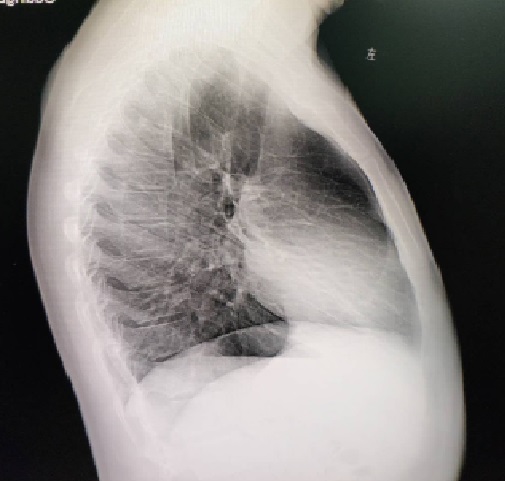

术前

术前X线